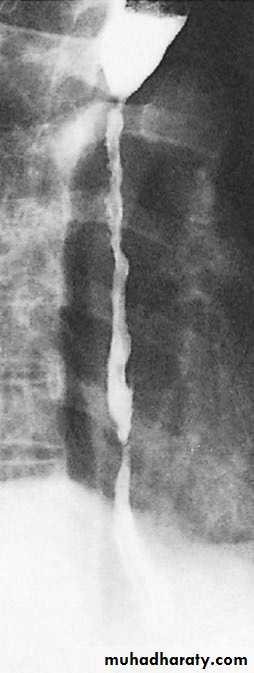

Figure 2: normal barium swallow of esophagus.

Figure 7: stricture following corrosive injury.